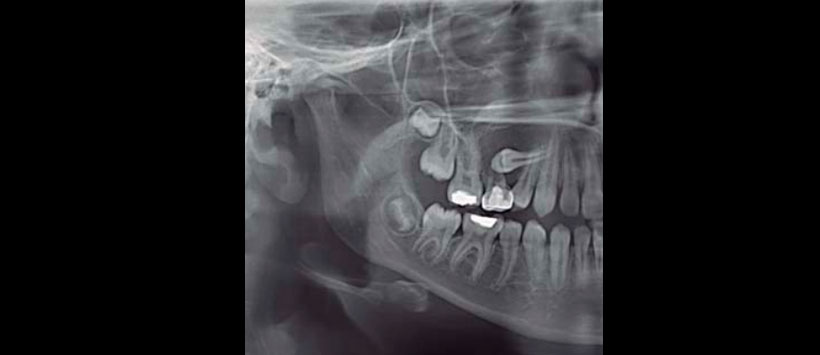

Imagenológicamente en la ortopantomografía se observó una zona radiolúcida unilocular circunscrita bien delimitada, con borde radiopaco bien definido, segundo premolar incluido en posición horizontal. Segundo molar deciduo con tratamiento pulpar. Tomografía de haz cónico: cortes axiales, sagitales, coronales y reconstrucción tridimensional mostraron quiste maxilar derecho de 2.6 cm de diámetro total, ocupando la tercera parte de la capacidad volumétrica de seno maxilar, desplazamiento de la pared anterior de seno maxilar y pared lateral de la fosa nasal derecha (Figuras 4 a 6).